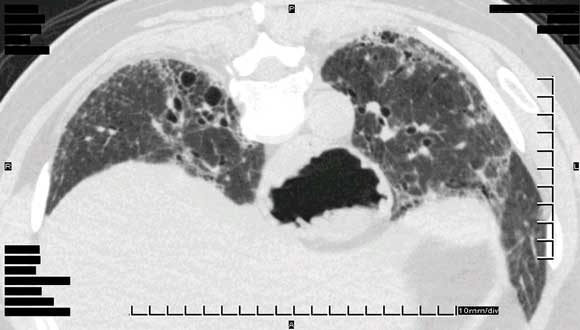

Pneumonitis was diagnosed based on clinical assessment, along with demonstration of interstitial infiltrates on high-resolution computed tomography and reduced transfer factor for carbon monoxide diffusion on lung function testing (Box 3).

Our patients shared many features with these patients. However, we did not observe rash of a dermatomyositic, lupoid or urticarial type, or lupus or polymyositis-like syndromes in our patients. Instead, all presented with respiratory symptoms — shortness of breath with or without dry cough — generally of insidious onset. Two out of six patients tested were positive for ANA with no other clinical features of connective tissue disease. The findings on transbronchial biopsy, when performed, were non-specific. Radiological appearances varied between alveolitis and fibrosis, but none showed the characteristic subpleural basal honeycombing that is common in usual interstitial pneumonia. The occurrence of alveolar eosinophilia in two out of the four patients who underwent bronchoalveolar lavage, which has previously been described in drug-hypersensitivity pneumonitis, and the response in several patients to drug cessation and/or corticosteroid therapy also point to a potential drug-induced pneumonitis.